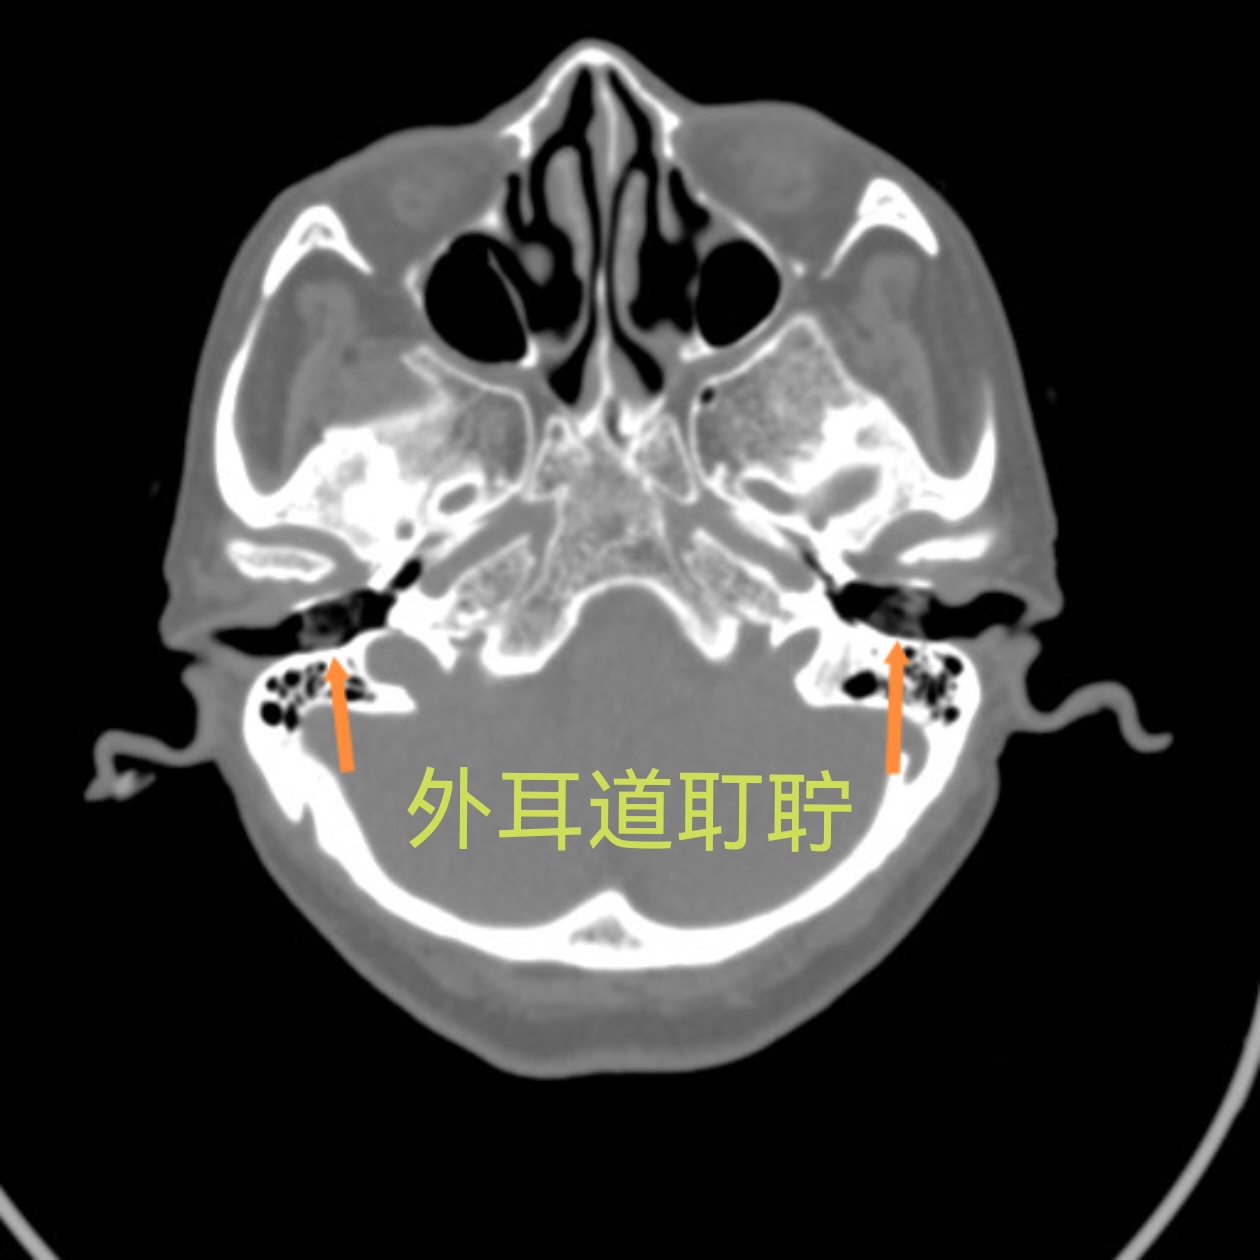

反复出现奇怪晕厥病因成谜查房时这个细节点醒医生

昨天不小心摔了一跤,磕到头了, 过来做了个ct